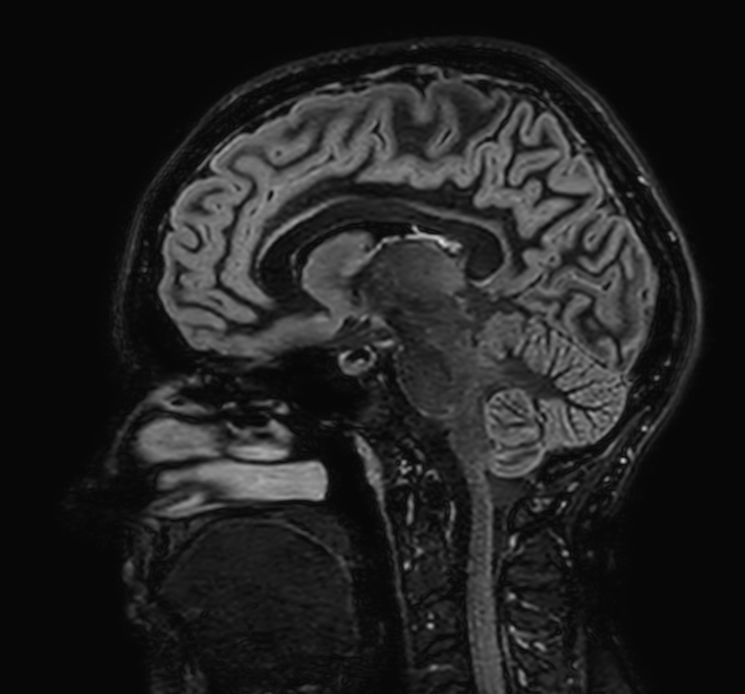

Sagittal 3D Double IR

Sagittal 3D T2w TSE